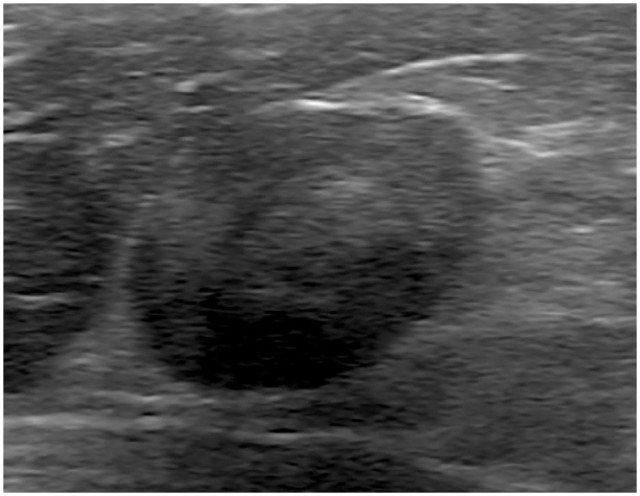

Case summary: Persistent and progressive weakness secondary to hypokalaemia, that is, hypokalaemic polymyopathy, is one of the most common clinical signs of primary hyperaldosteronism (PHA). Herein, we report a case of PHA with infraspinatus muscle necrosis. A 5-year-old castrated male domestic shorthair cat presented with a history of polyuria and polydipsia, decreased activity, staggering gait, difficulty in jumping and inward rotation of both forelimbs. Blood examination revealed hypokalaemia, increased serum creatinine kinase activity and high serum aldosterone concentration. Abdominal ultrasonography and CT revealed an enlarged right adrenal gland. Post-contrast thoracic CT showed peripheral contrast enhancement and a non-enhanced centre in the bilateral infraspinatus muscles. From the day of initial presentation, the cat was started on oral potassium replacement therapy. On day 17, the right adrenal gland was surgically resected and the left infraspinatus muscle was biopsied. Histopathological examination confirmed the presence of an adrenocortical adenoma in the right adrenal gland and necrosis of the muscle fibres in the left infraspinatus muscle. On day 29, all clinical signs had disappeared, and the serum potassium concentration, creatinine kinase activity and aldosterone concentration had normalised. On day 57, atrophy of the bilateral infraspinatus muscles was noted, but there was no evidence of any posture or gait abnormalities.